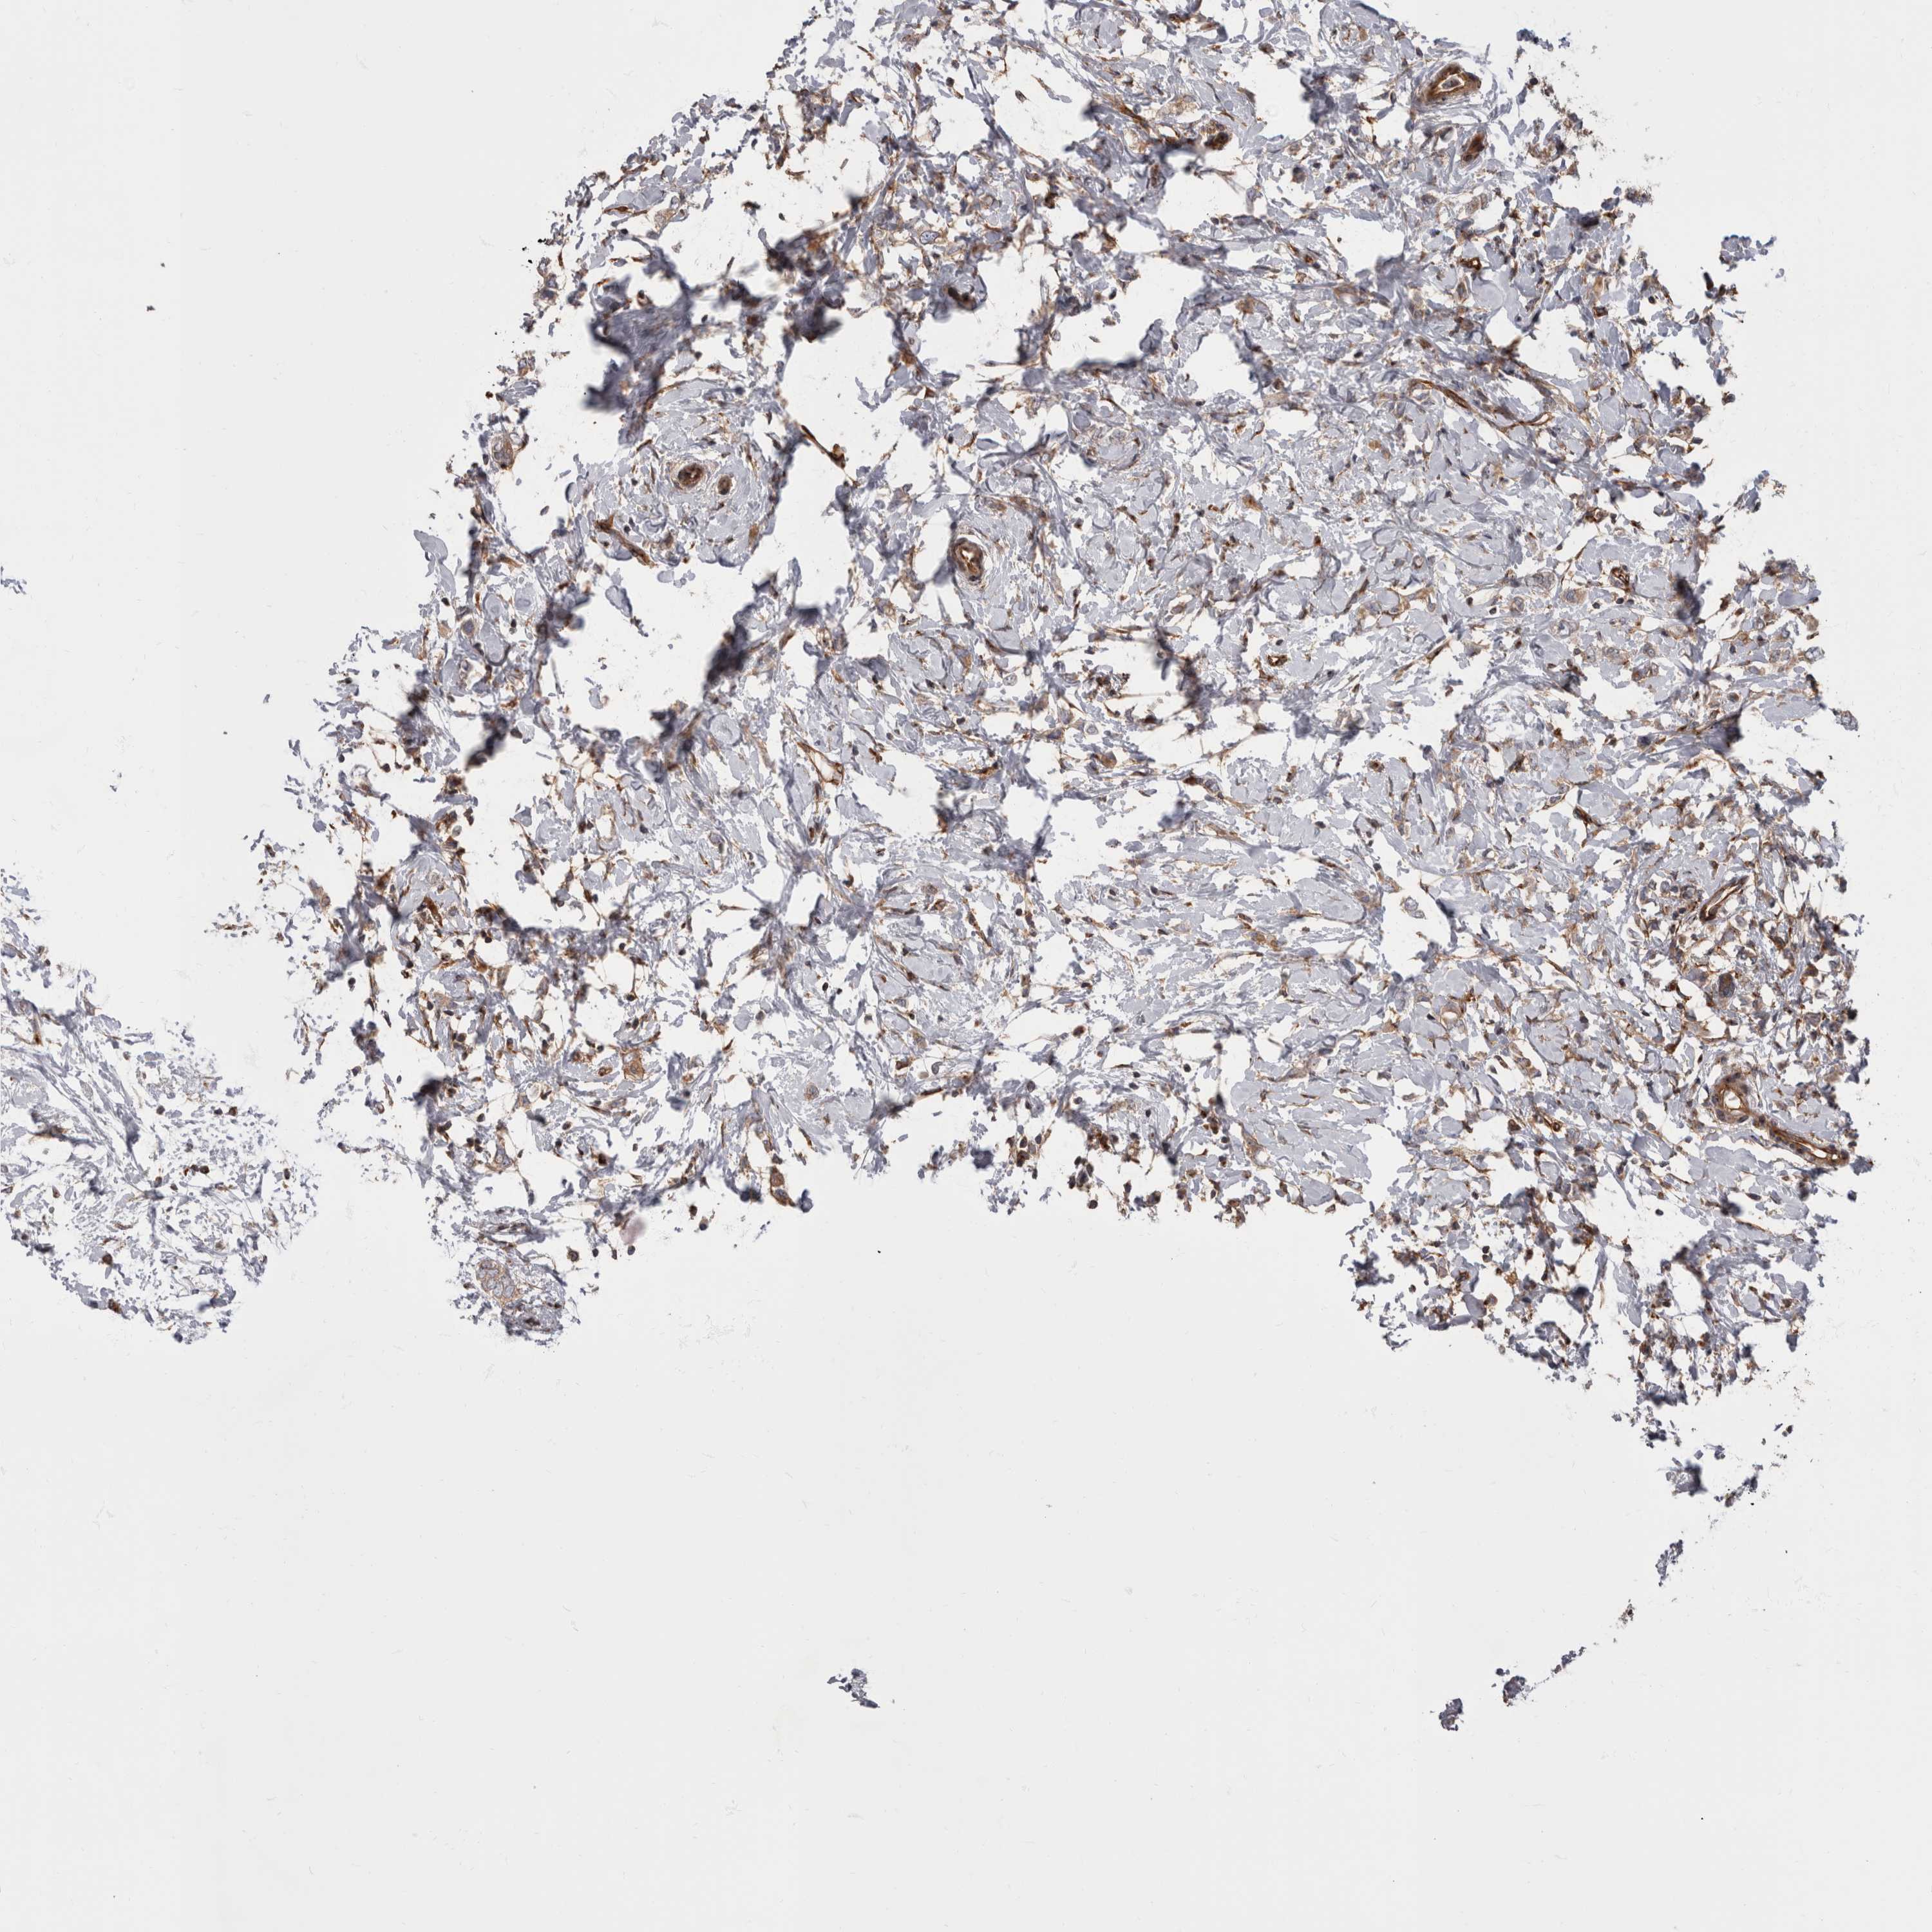

CANCER BREAST CANCER Show tissue menu

BRCA TCGA BRCA VALIDATION PROTEIN EXPRESSION